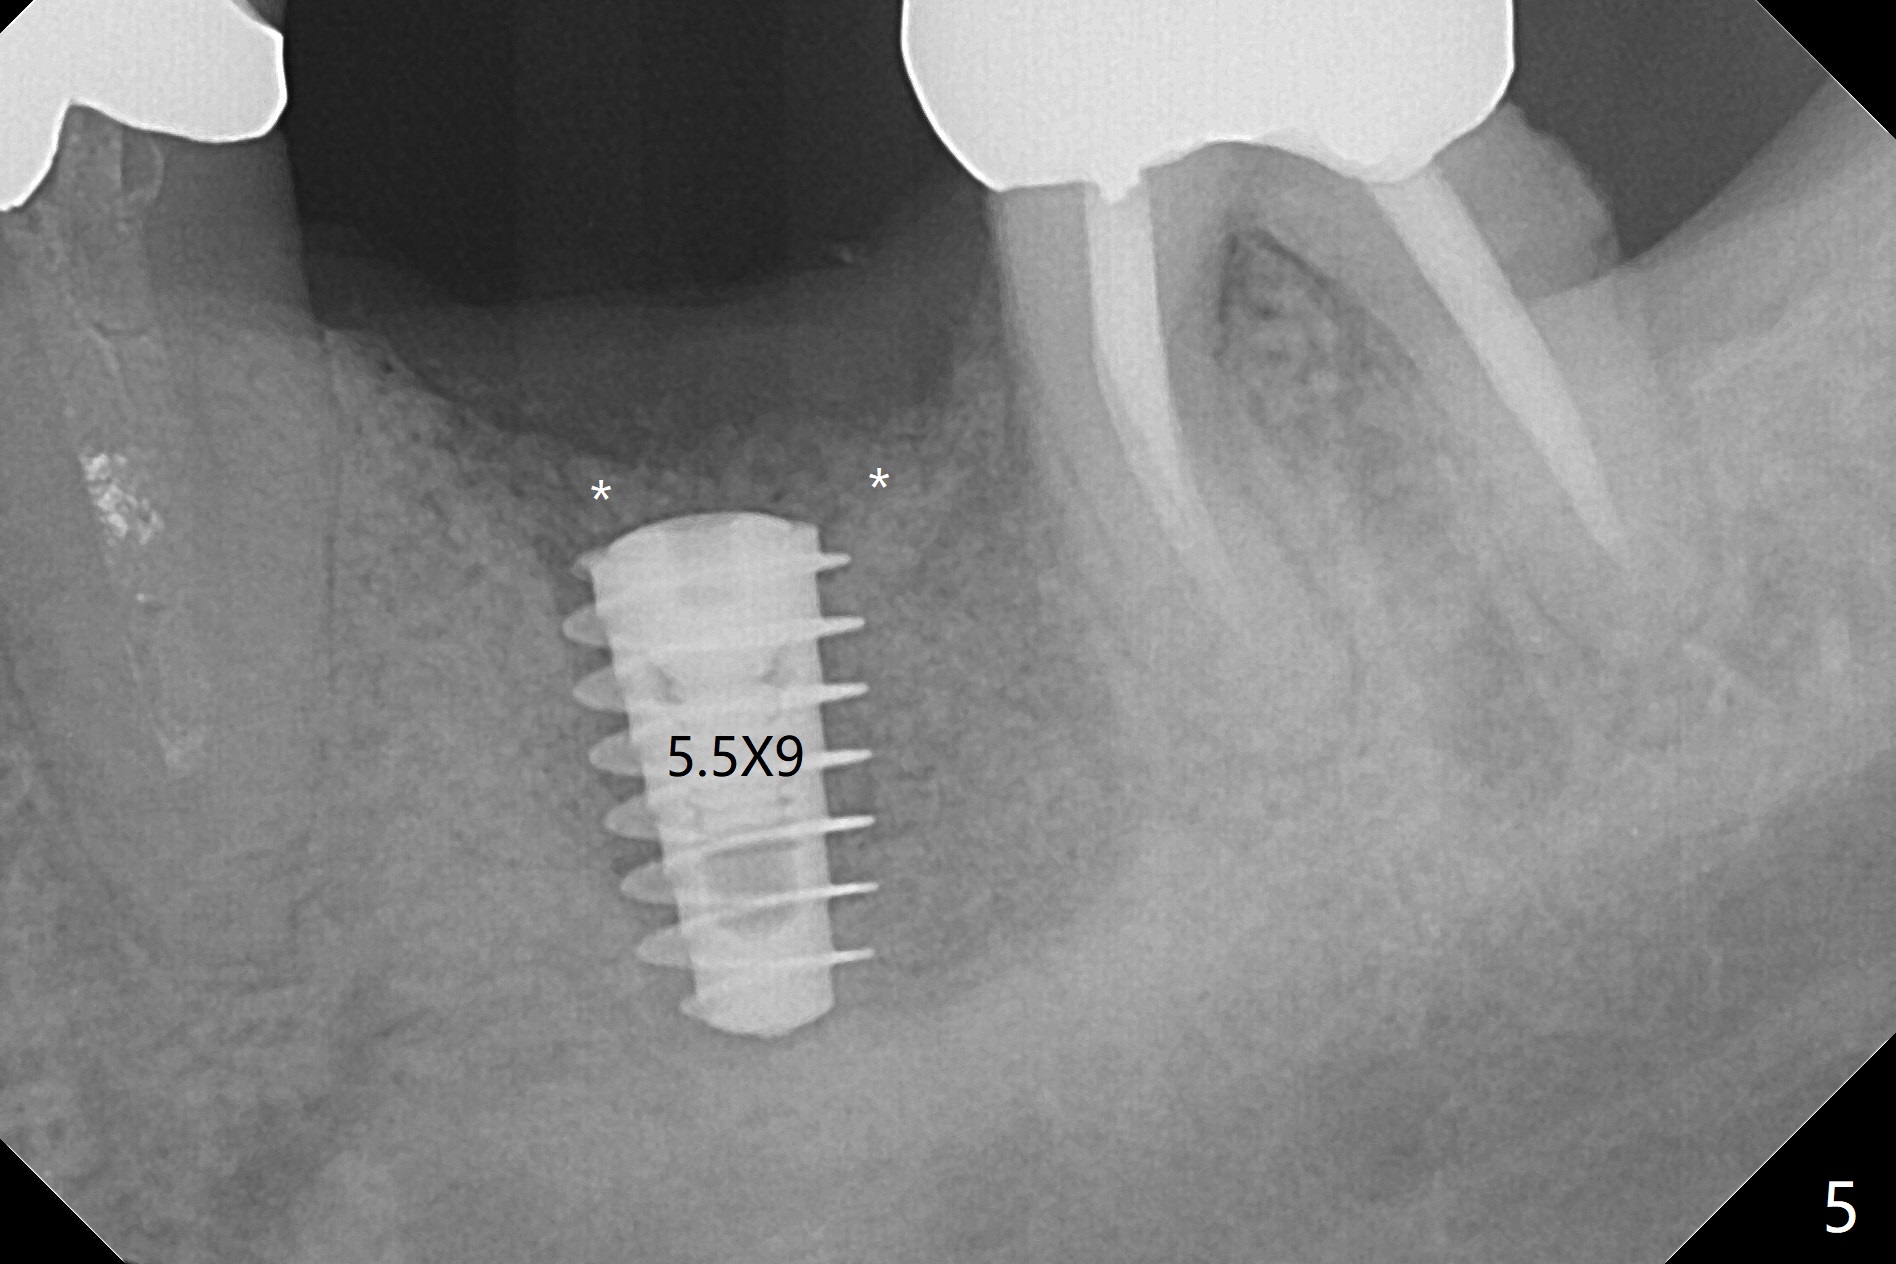

When the patient returns 4 months post implant removal and bone graft, the ridge at #19 is concave with a small hole which communicates with the underlying bone (Fig.1 <). The low density bone in the middle of the socket is ignored (Fig.2 *, 3 S (soft)). With under drilling, primary stability of tissue-level taps is lower. A bone-level dummy implant is placed with low torque (Fig.4). After removal of granulation tissue distal to the osteotomy, a larger implant is inserted with ~15 Ncm; mixture of autogenous bone and allograft is packed (Fig.5 *). The latter is covered by 12x12 mm BioXclude and sutured with 4/0 Chromic Gut tension free. 植牙后6.5月牙槽嵴饱满,角化龈宽(图六(刚开始浸润麻醉))。术后6.5月切开证实植体上面没有骨质覆盖(如图七:*),第一螺纹可能暴露(>)。由于骨质吸收,大号基台置入没阻挡,或者困难(图八),第一螺纹暴露(>)需要再次植骨(图九:*)。放置大号基台(6x6(4)毫米)和植骨使萎缩牙槽嵴部分得到修复(图十,与Uncover前(图六)对比)。Uncover时即刻置入修复性基台好处是利用基台牙龈外部分强化牙周敷料固定,基台中央放置一个棉球后,敷料可以插入基台中央进一步增加固位(图十一(舌侧观):*)。